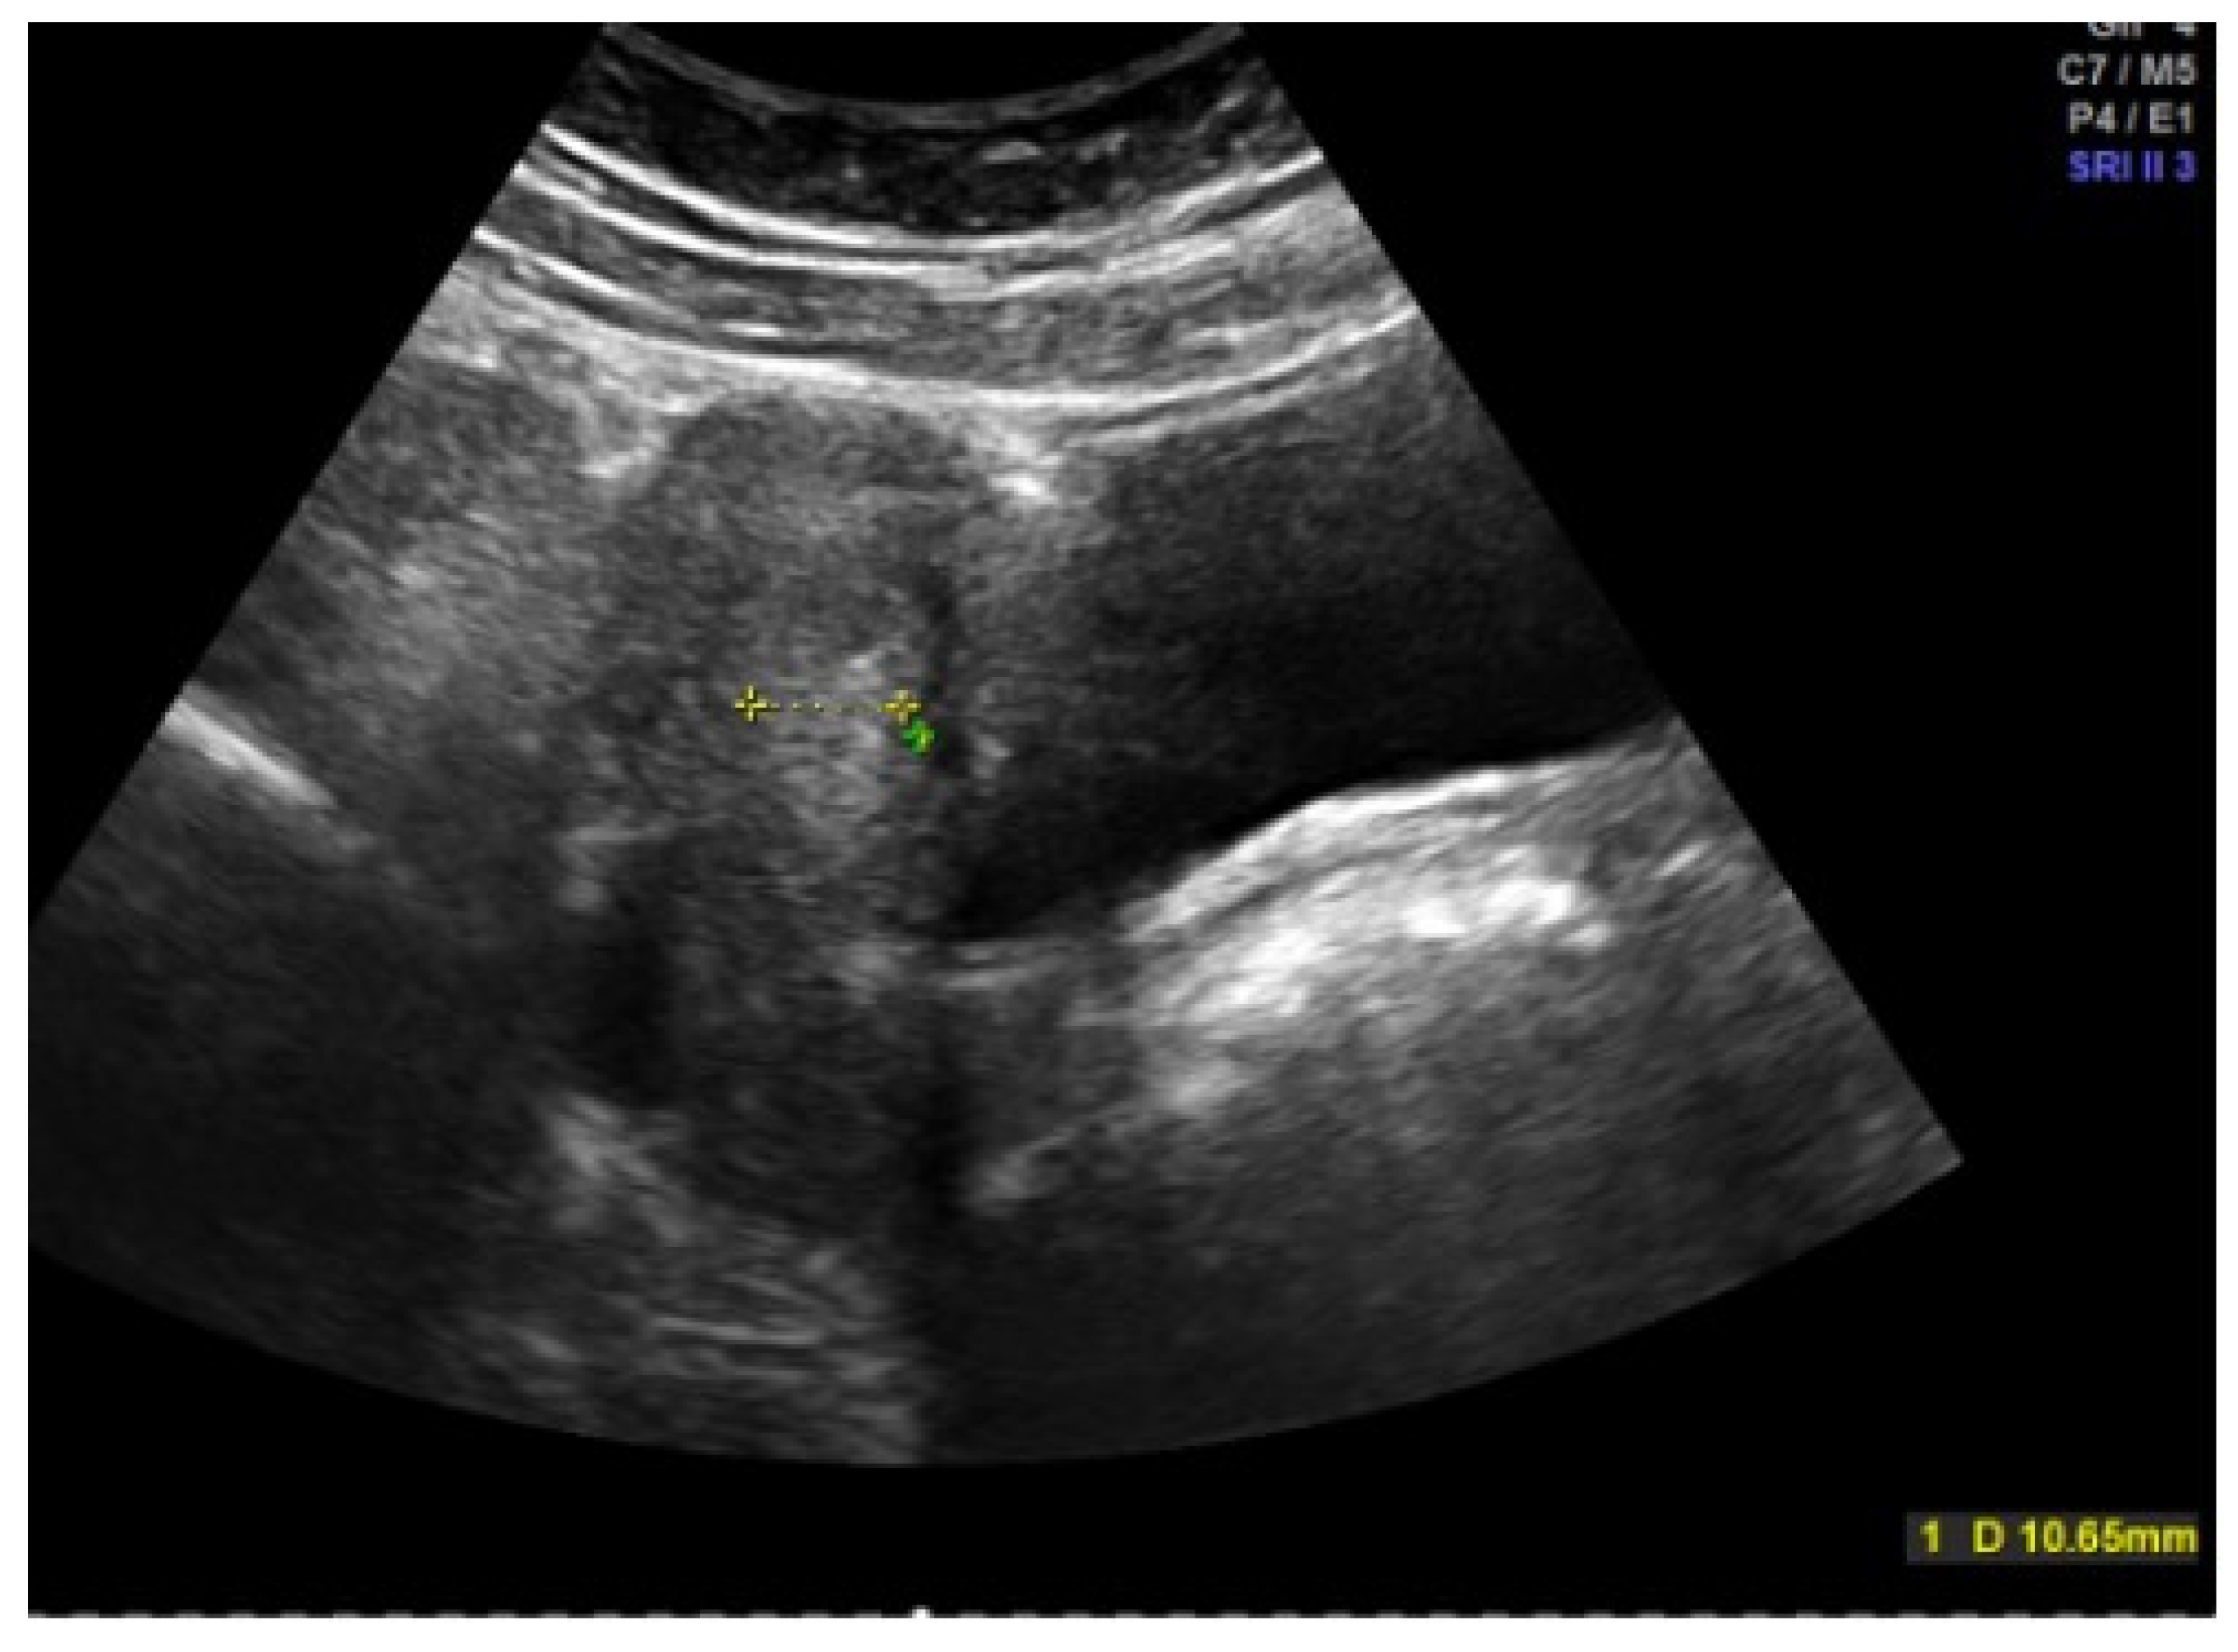

Hormonal therapy is the treatment of choice [11,19]. After a sonographic assessment of the endometrial thickness (Figure 4 and Figure 5), progestogen monotherapy can be administered for 14 days (e.g., dydrogesterone 2 × 10 mg daily, medroxyprogesterone acetate 10 mg daily) in the case of an excessively thickened endometrium. If the endometrium is thin, there are various options. In this case, estrogenization of the endometrium with subsequent transformation must take place first. One option would be estrogen monotherapy for 10 days, followed by an estrogen–progestogen combination, as found in oral hormone replacement therapies. Another option, and the most commonly used, especially because of its prophylactic function, is an oral contraceptive [11]. In an acute situation, a high-dose contraceptive pill containing at least 30 µg of ethinylestradiol can be administered every 6–8 h until the bleeding intensity decreases, followed by a reduction to two and then one tablet daily if the bleeding cannot be stopped with the usual dosage [6]. The patient’s individual risk factors and contraindications must be taken into account. A progesterone-only pill can also be administered depending on the risk profile. A higher dosage of progestogens may also be necessary in the case of acute heavy bleeding, e.g., double the dose of desogestrel [5,6,20]. The third option is 2.5–5 mg of norethisterone acetate daily for 10 days, which, as a progestogen with an estrogenic partial effect, addresses both the thickening and transformation of the endometrium, but this is no longer freely available in all countries [16,21,22]. In rare cases, hospitalization may be necessary, especially if the hemoglobin level is already below 8 g/dL [6].

Figure 5.

Abdominal sonography: Messurement of Excessively thickened endometrium in a 12-year-old girl with juvenile hypermenorrhea (photo by the authors).